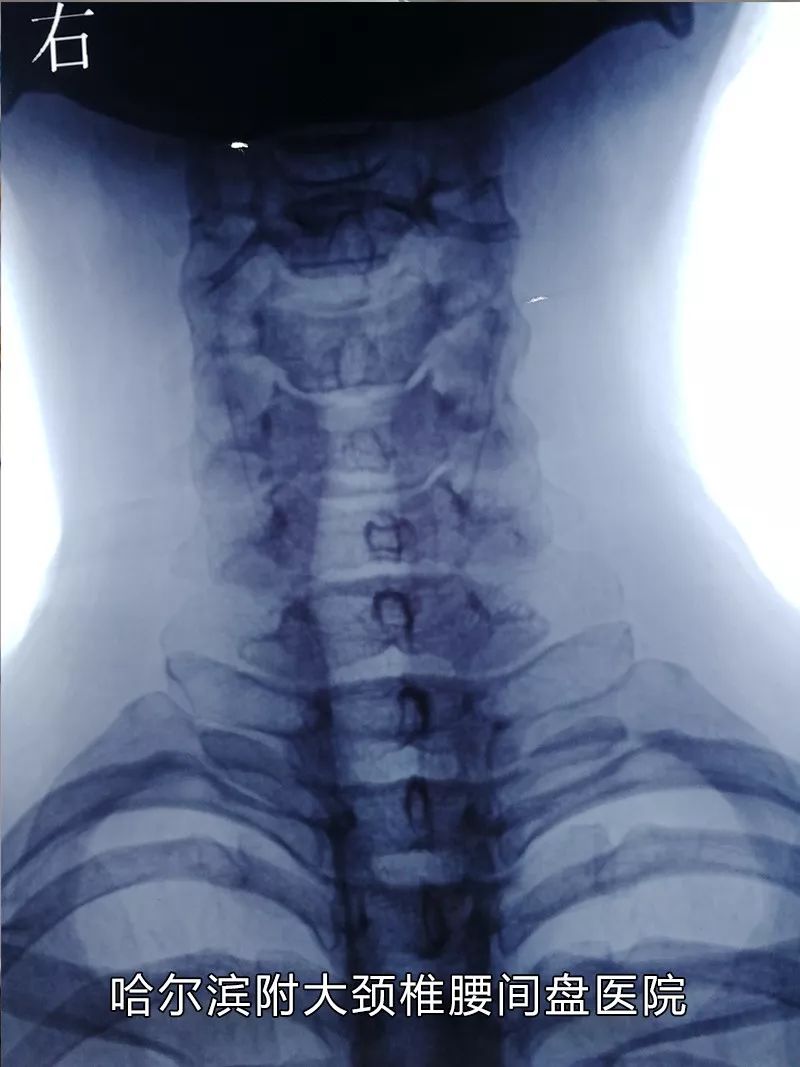

哈尔滨附大颈椎腰间盘医院业务院长刘达生介绍,腰椎间盘突出症呈现年轻化的趋势,这与当代人工作、生活方式息息相关,久坐久站、睡姿不正确、缺少运动等不良生活习惯,容易诱发或导致腰椎间盘突出症。

哈尔滨附大颈椎腰间盘医院业务院长、会诊中心主任

长期从事颈椎病、腰间盘突出、椎管狭窄等骨科疾病的治疗